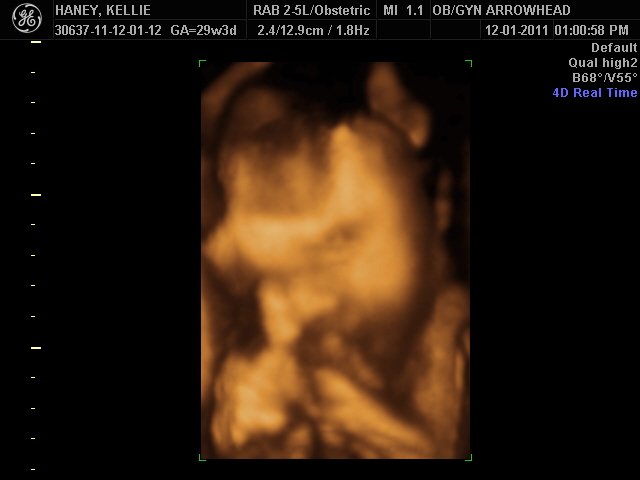

We offer complimentary 3D/4D Ultrasounds to all our OB patients around 30 weeks! The following photos are some examples of our work, shown with permission from our patients.